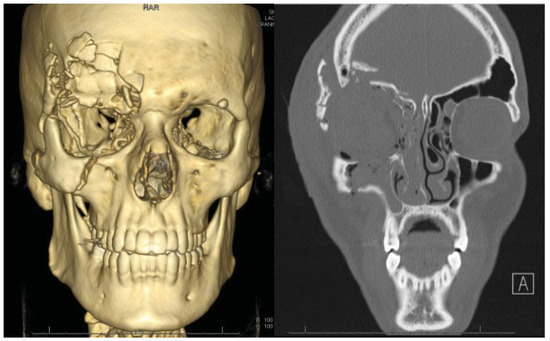

Case 2

A 27-year old man who presented at the emergency room after a rocket exploded on his right eye on January 1, 2012. The patient was hemodynamically stable on presentation. He could not remember the impact and according to bystanders, the patient was unconscious for several minutes. Substantial periorbital swelling and a laceration above the right eye was seen, and the sensibility of the right cheek was diminished. The ophthalmologist was not able to open his right eye and proper examination of vision was not possible at that moment. During further investigation, the CT scan showed an extensive blow-out fracture of the right orbit, with involvement of all orbital walls and the infraorbital canal (Figure 5). The right globe was completely ruptured. The fracture extended cranially into the frontal sinus, with fracturing of the internal and external wall. Multiple bone fragments were displaced intracranially, accompanied by a subarachnoidal hemorrhage and multiple cerebral contusions. Also, a zygomaticomaxillary complex fracture was described. Consultation of oral and maxillofacial surgery, neurosurgery, and ophthalmology was obtained. The patient was brought to the operating room instantly, and an evisceration of the right eye was performed by the ophthalmology team (Figure 6). On hospital day 4, the swelling was significantly less and management of the facial fractures was performed. Via a coronal incision, the right frontal sinus was approached. The neurosurgery service performed a craniotomy and closed several dura leaks. Next, the posterior wall of the frontal sinus was removed and the nasofrontal duct obliterated, thereby achieving cranialization of the right frontal sinus. Bone fragments of posterior wall were used for reconstruction of the anterior frontal sinus wall and the defects in the orbital walls (Figure 7). The zygoma fracture was reduced and fixated. Recovery was uncomplicated and patient was discharged after several days of observation. A month posttrauma, an acrylic ocular implant was placed by the ophthalmology team. The result was esthetically suboptimal, due to the acquired enophtalmic state of the right orbit. For this reason, reconstructive surgery was performed 18 months posttrauma, in which the right orbital floor was reconstructed using a titanium mesh plate. In the same session, an entropion correction was done by the ophthalmology service (Figure 8). Sensibility of the regions enervated by the second and third trigeminal branch remained disturbed due to damage of these nerves.

Figure 5. Preoperative three-dimensional reconstruction image (left) and computed tomography scan (right) of patient 2.